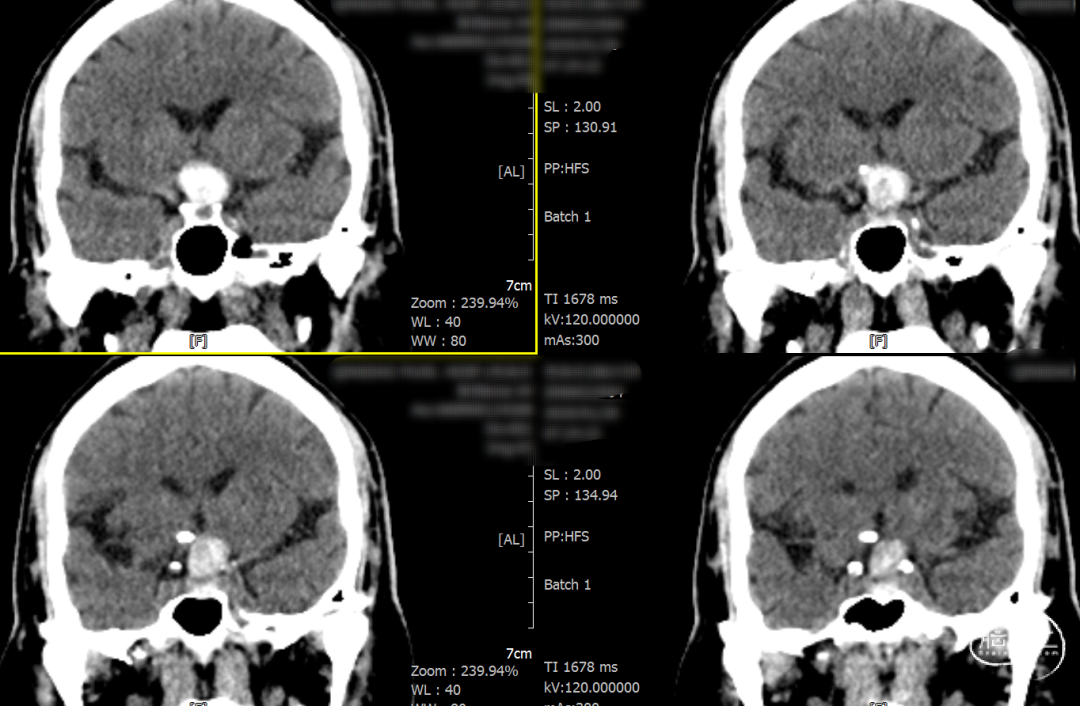

辅助检查示:2025-01-08 鞍区及垂体MR平扫:鞍内及鞍上肿瘤,垂体瘤并卒中?建议鞍区及垂体MR增强扫描。

2025-1-19 DSA造影3D重建及方案讨论:

DSA造影3D重建测量

术后一天检查。